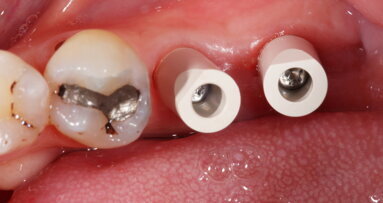

Fig. 1: Pre-treatment clinical photograph of tooth #11. (All images: Dr Michael R. Norton)

On examination, the patient presented with a minimally restored dentition with a few composite restorations and a crown on tooth #11. The tooth being in the aesthetic zone increased the challenge of delivering a good outcome. The patient had a healthy periodontium and only a few isolated non-pathological pockets of 4–5 mm in depth at the lingual surfaces of the mandibular molars, accompanied by some minor bleeding on probing. The patient was advised to seek more regular hygiene focusing on these areas.

Tooth #11 was immobile and associated with adequate ridge width and a wide band of keratinised tissue (Fig. 1). There was also a favourable Class I incisor relationship and adequate space to accommodate an implant-supported restoration. A CBCT scan of the site revealed an inadequately endodontically treated tooth with a lack of an apical seal and incomplete obturation of the canal. The tooth benefited from good bone support provided by a robust facial bone plate at the alveolar crest (Fig. 2), but there was a large periapical dentigerous cyst measuring approximately 10 × 8 mm, extending to the mesial surface of tooth #12, and complete fenestration of the facial plate superiorly (Fig. 3). The prognosis of the tooth was deemed to be hopeless, and extraction was indicated.